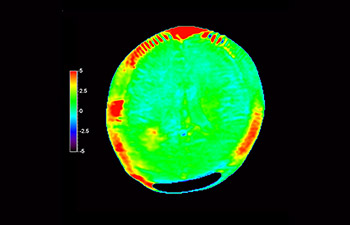

Imágenes cerebrales de recidiva del glioblastoma

con 3D APT